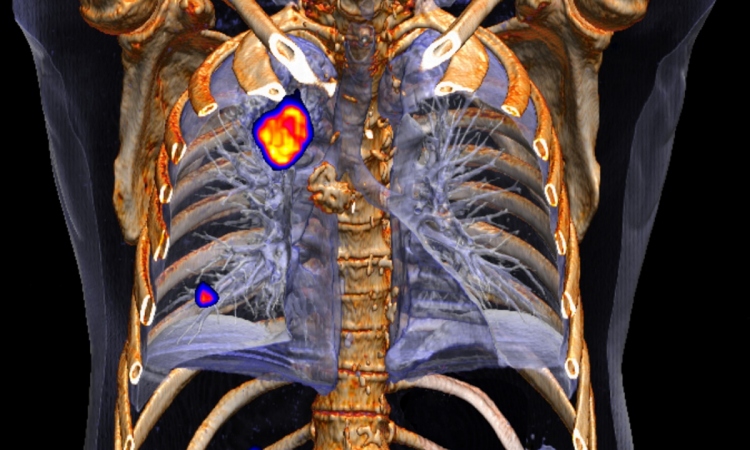

PET/CT, the combination of positron-emission-tomography and CT, and SPECT/CT, the combination of single photon emission CT and CT, are already fixed components of radiological and nuclear medical diagnosis. However, there are also new developments in this area of medicine.

Researchers from the Statistical Imaging Group at University College Cork, Ireland, as well as researchers from the Department for Radiology and the PET/CT Unit at the University Hospital Cork, reported on statistical methods they have developed to analyse 18F-FDG-PET/CT examinations.

With the help of the tracer 18F-fludeoxyglucose a lot more information can be gained about heterogeneous tumours than with conventional PET/CT. Lung cancer for instance is characterised by a particularly high tumour heterogeneity, i.e. the tumours contain a number of genetically different cancer cells with different biological characteristics – a fact that must considered during treatment.